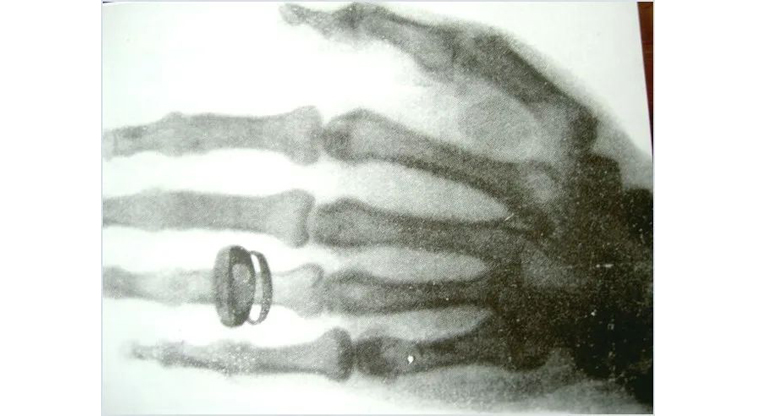

他在做当时欧洲很风靡的阴极射线实验时,发现已经用黑布包起来只留下一个狭缝的阴极射线管前方涂有亚铂氰化钡的荧光屏,会闪亮一下,反复验证确实总是如此,他不得其解。第一个问题,当时已知道阴极放电是稀薄气体在高压中产生的可见光,既然用黑纸把它包住了,使荧光屏发亮的一定是看不见的光了。他把自己关在实验室里几个礼拜,反复各种固体、液体物质来遮挡这奇怪的射线,最后还是真没搞清楚这到底是什么,为什么?唯一清楚的是这种现象不是当时已知的任何射线,所以就以代表未知的字母X命名为X-射线。这是给他往实验室送饭的夫人在帮着他移动荧光屏,看射线随距离变化的影响时,突然看到自己的手的骨骼像了,还有手上的戒指,以为见鬼了,吓得把荧光屏都摔到桌子上。这就是人类历史上第一张X-光的照片。

年底前,伦琴向维尔兹堡物理和医学学会递交了一篇通讯文章《一种新射线--初步报告》,还把这张照片印到自己给朋友的圣诞节贺卡上,后经过报纸披露,轰动世界。之后有很多人向他来购买专利,德国一位王子甚至愿用王位跟他换,伦琴说我的发现就要像阳光和空气一样无偿地为人类服务,这就是科学家的境界!伦琴因X射线的发现,获得了1901年颁发的第一个诺贝尔奖。